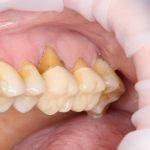

В общем, так и получилось. Уж не помню, почему я наобещал пациентке, что мы поставим ей имплантаты одновременно с остеопластикой. Но я наобещал. И, когда увидел клиническую картину в полости рта:

у меня появились серьезные сомнения, смогу ли я выполнить своё обещание. Вот только не спрашивай меня «Вот чо, сложно было по КЛКТ посмотреть?». Я же не спрашиваю тебя, где ты был в 2013 году, и сделал ли ты домашку. Но, в целом, план операции у нас не поменялся. Как и было оговорено, мы проведем остеопластику с одновременной имплантацией в боковом участке нижней челюсти справа.

Кстати, обрати внимание на ширину альвеолярного гребня (левая картинка). Она чуть меньше 3 мм. Это объясняет, почему я засомневался в возможности установки имплантатов одновременно с остеопластикой. Понятно и без КЛКТ.